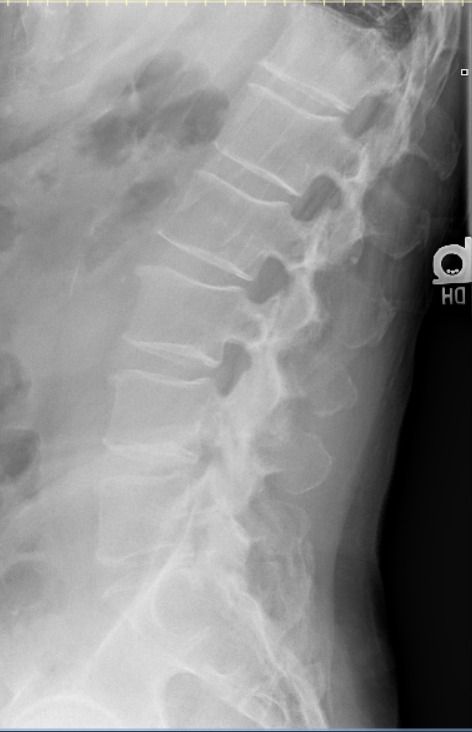

Approximately 10 weeks later the patient reported injury to the low back while carrying a large, heavy object and stepping down, resulting in moderate, non-radiating pain with both rest and activity. Radiographic examination of the lumbar spine revealed a compression fracture of the inferior aspect of L3 with step defect, possibly acute, and ununited left L2 and L3 transverse processes, age indeterminate. The patient was referred for DEXA bone density examination and cross-sectional imaging (CT) to further evaluate the extent of the L3 compression fracture.

Chiropractic care using Thompson drops in unaffected spinal regions continued for the next 5 weeks. After a 7-month absence from care, the patient returned reporting midline and centrally worsening non-radiating low back pain after a fall on his back and buttocks approximately 3-4 months prior in his bathroom. He was seen by his medical doctor prior to the treatment visit for this incident and had been referred to physical therapy. He denied head injury, fracture, loss of consciousness, saddle paresthesia or changes with bowel and bladder function. Radiographic examination of the lumbar spine demonstrated superior and inferior endplate fractures of the T12 vertebral body with 60% vertical loss of height not evident on previous examination. Osteoporosis was reported at this time. Examination with CT and MRI were recommended for further characterization of the T12 compression fracture due to the severity of radiographic presentation. The patient was referred to his primary care physician for co-management and the provider was contacted directly due to the loss of vertebral body height (see Table 1 for overview of progression of care).